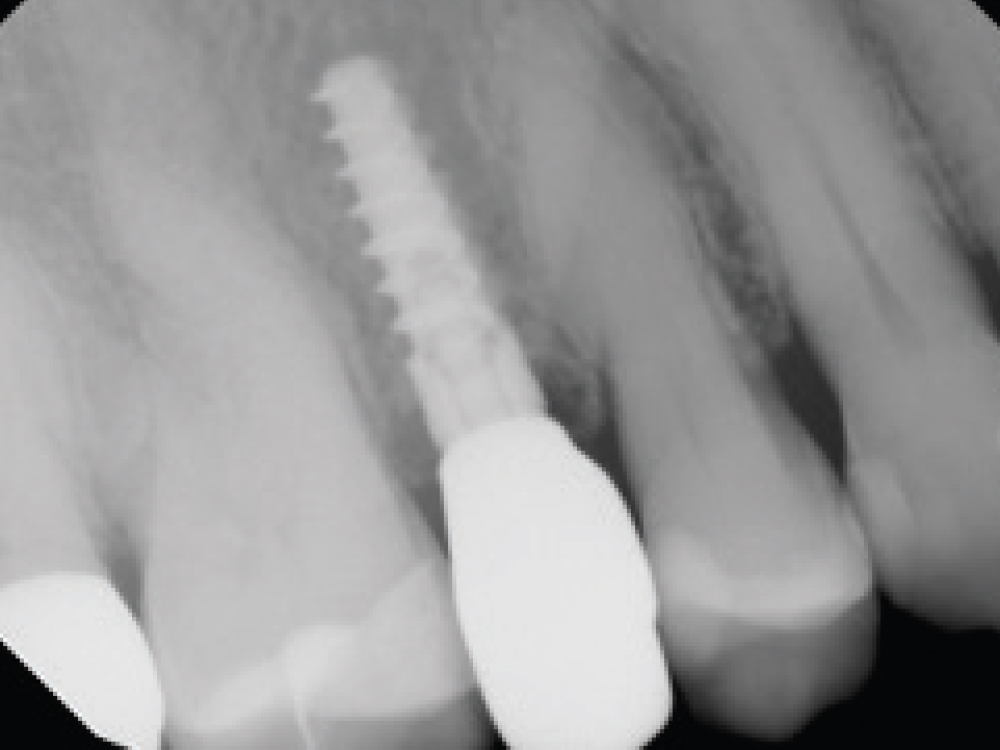

The initial evaluation of the patient should include screening for bony defects in sites considered for implant placement. During intraoral examination, you may be able to identify a “soft spot” on the facial or buccal plate while palpating the soft tissue adjacent to the roots of the tooth. When reviewing the patient’s periapical radiograph, examine the apices of the tooth’s roots. If a radiolucency is present, then the site should be evaluated for a possible bone fenestration.

If a fenestration is suspected, it is imperative to complete a preoperative CBCT evaluation. CBCT scanning is a valuable tool for determining the thickness of the buccal plate. In particular, a series of cross-sectional CBCT images should be evaluated to determine the extent of the fenestration and whether the pathology extends through the buccal plate. These images are also useful in determining if there is sufficient bone to immediately place the implant at the time of extraction or, if instead, the site should be grafted and treated following a delayed implant placement protocol.

CBCT Scan fenestration

Premolar extraction of fenestration

Preoperative cross-sectional CBCT scan confirming fenestration at the site of a premolar requiring extraction, and buccal view of the exposed defect following flap reflection.